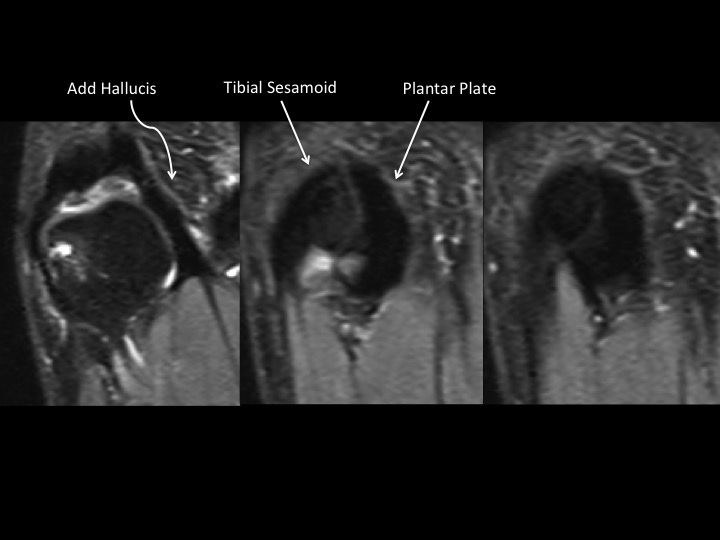

31F 5 years pain, evaluate sesamoid AVN

In the AP XR, the fibular sesamoid is not visible, but in the sesamoid view, its diminutive, smooth and not sclerotic. This leads me to believe that this is marked hypoplasia rather than AVN. Hallucal sesamoid variants are common. Aplasia is uncommon. Hypoplasia is not rare, but this degree of hypoplasia seems unusual. Based on the images, it seems there is compensatory thickening of the fibular portion of the plantar plate (sesamoids are embedded in the plantar plate). Structures stay where they are supposed to be: the tibial sesamoid is located and the FHL is midline in the short axis image. Shes had pain for 5 years....which I cannot explain, other than to say that normal variants may be symptomatic. The attached article is a little crazy, check it out. Reference article.